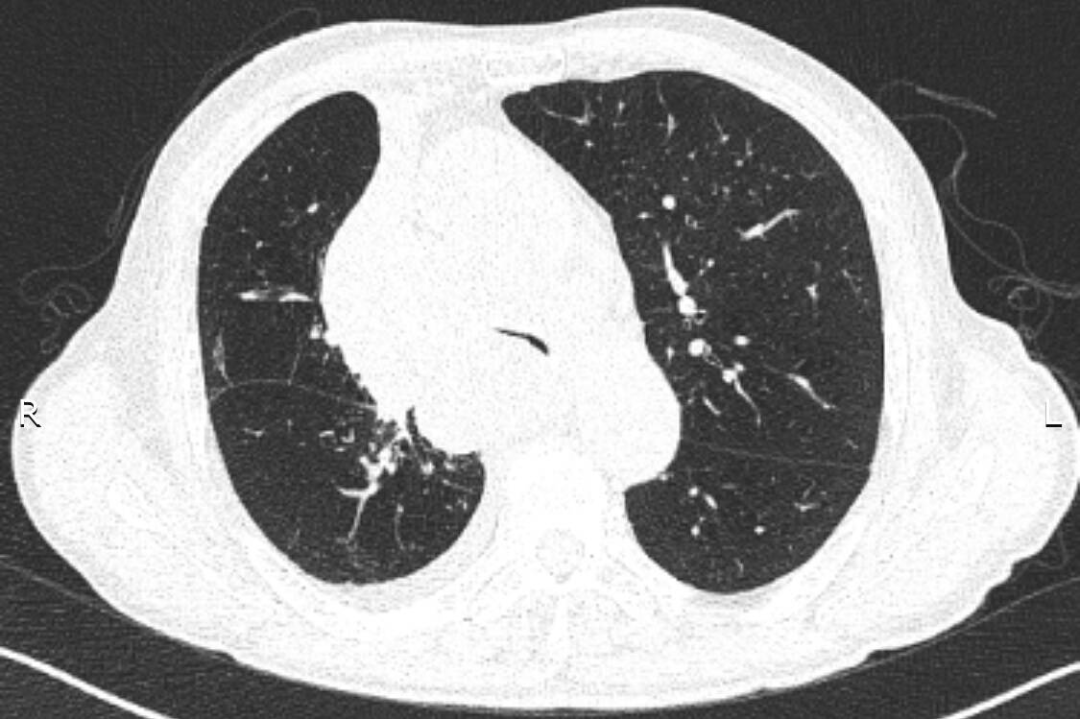

入院后給予吸氧、藥物治療,癥狀緩解不明顯。張強主任結合患者的癥狀、體征及CT表現,考慮憋喘主要為腫瘤浸潤壓迫氣道引起,緊急行電子氣管鏡檢查,明確了氣道被壓迫情況。正常成人氣管內鏡約2.5cm,患者氣管下段重度狹窄,直徑僅約3mm,而且狹窄一直延續到右主支氣管末端,左主支氣管狹窄情況還稍輕些。建議患者可緊急置入支氣管支架短期緩解癥狀,綜合支架特點、支架定制周期、患者病情、費用等情況后,家屬希望能為患者盡快放置硅酮支架。張強主任立即聯系醫務科,并聯系支架置入經驗豐富的外請專家王曉東教授前來指導,為患者保駕護航。

支架放置前:CT提示近圓形的氣管被壓迫至“一條縫”